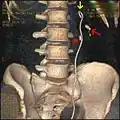

Tomografia komputerowa jamy brzusznej – rekonstrukcja 3D. Stent w lewym moczowodzie (żółta strzałka). Kamień zlokalizowany w miedniczce lewej nerki (górna czerwona strzałka) oraz kamień zlokalizowany w lewym moczowodzie poza stentem (dolna czerwona strzałka)